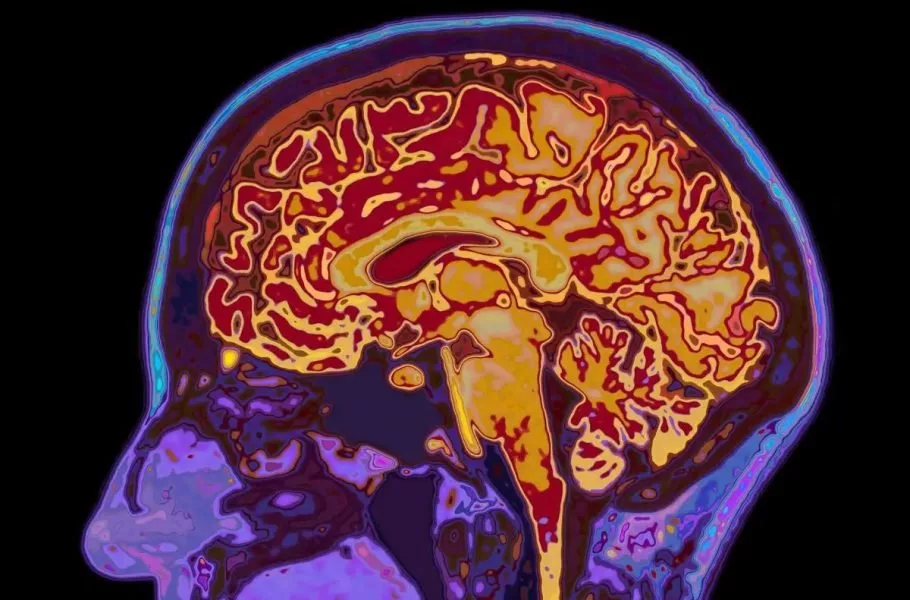

شوک علمی درباره مغز انسان؛ تا ۳۲ سالگی کامل نیستیم / پنج دوران اصلی رشد مغز انسان کدامند؟